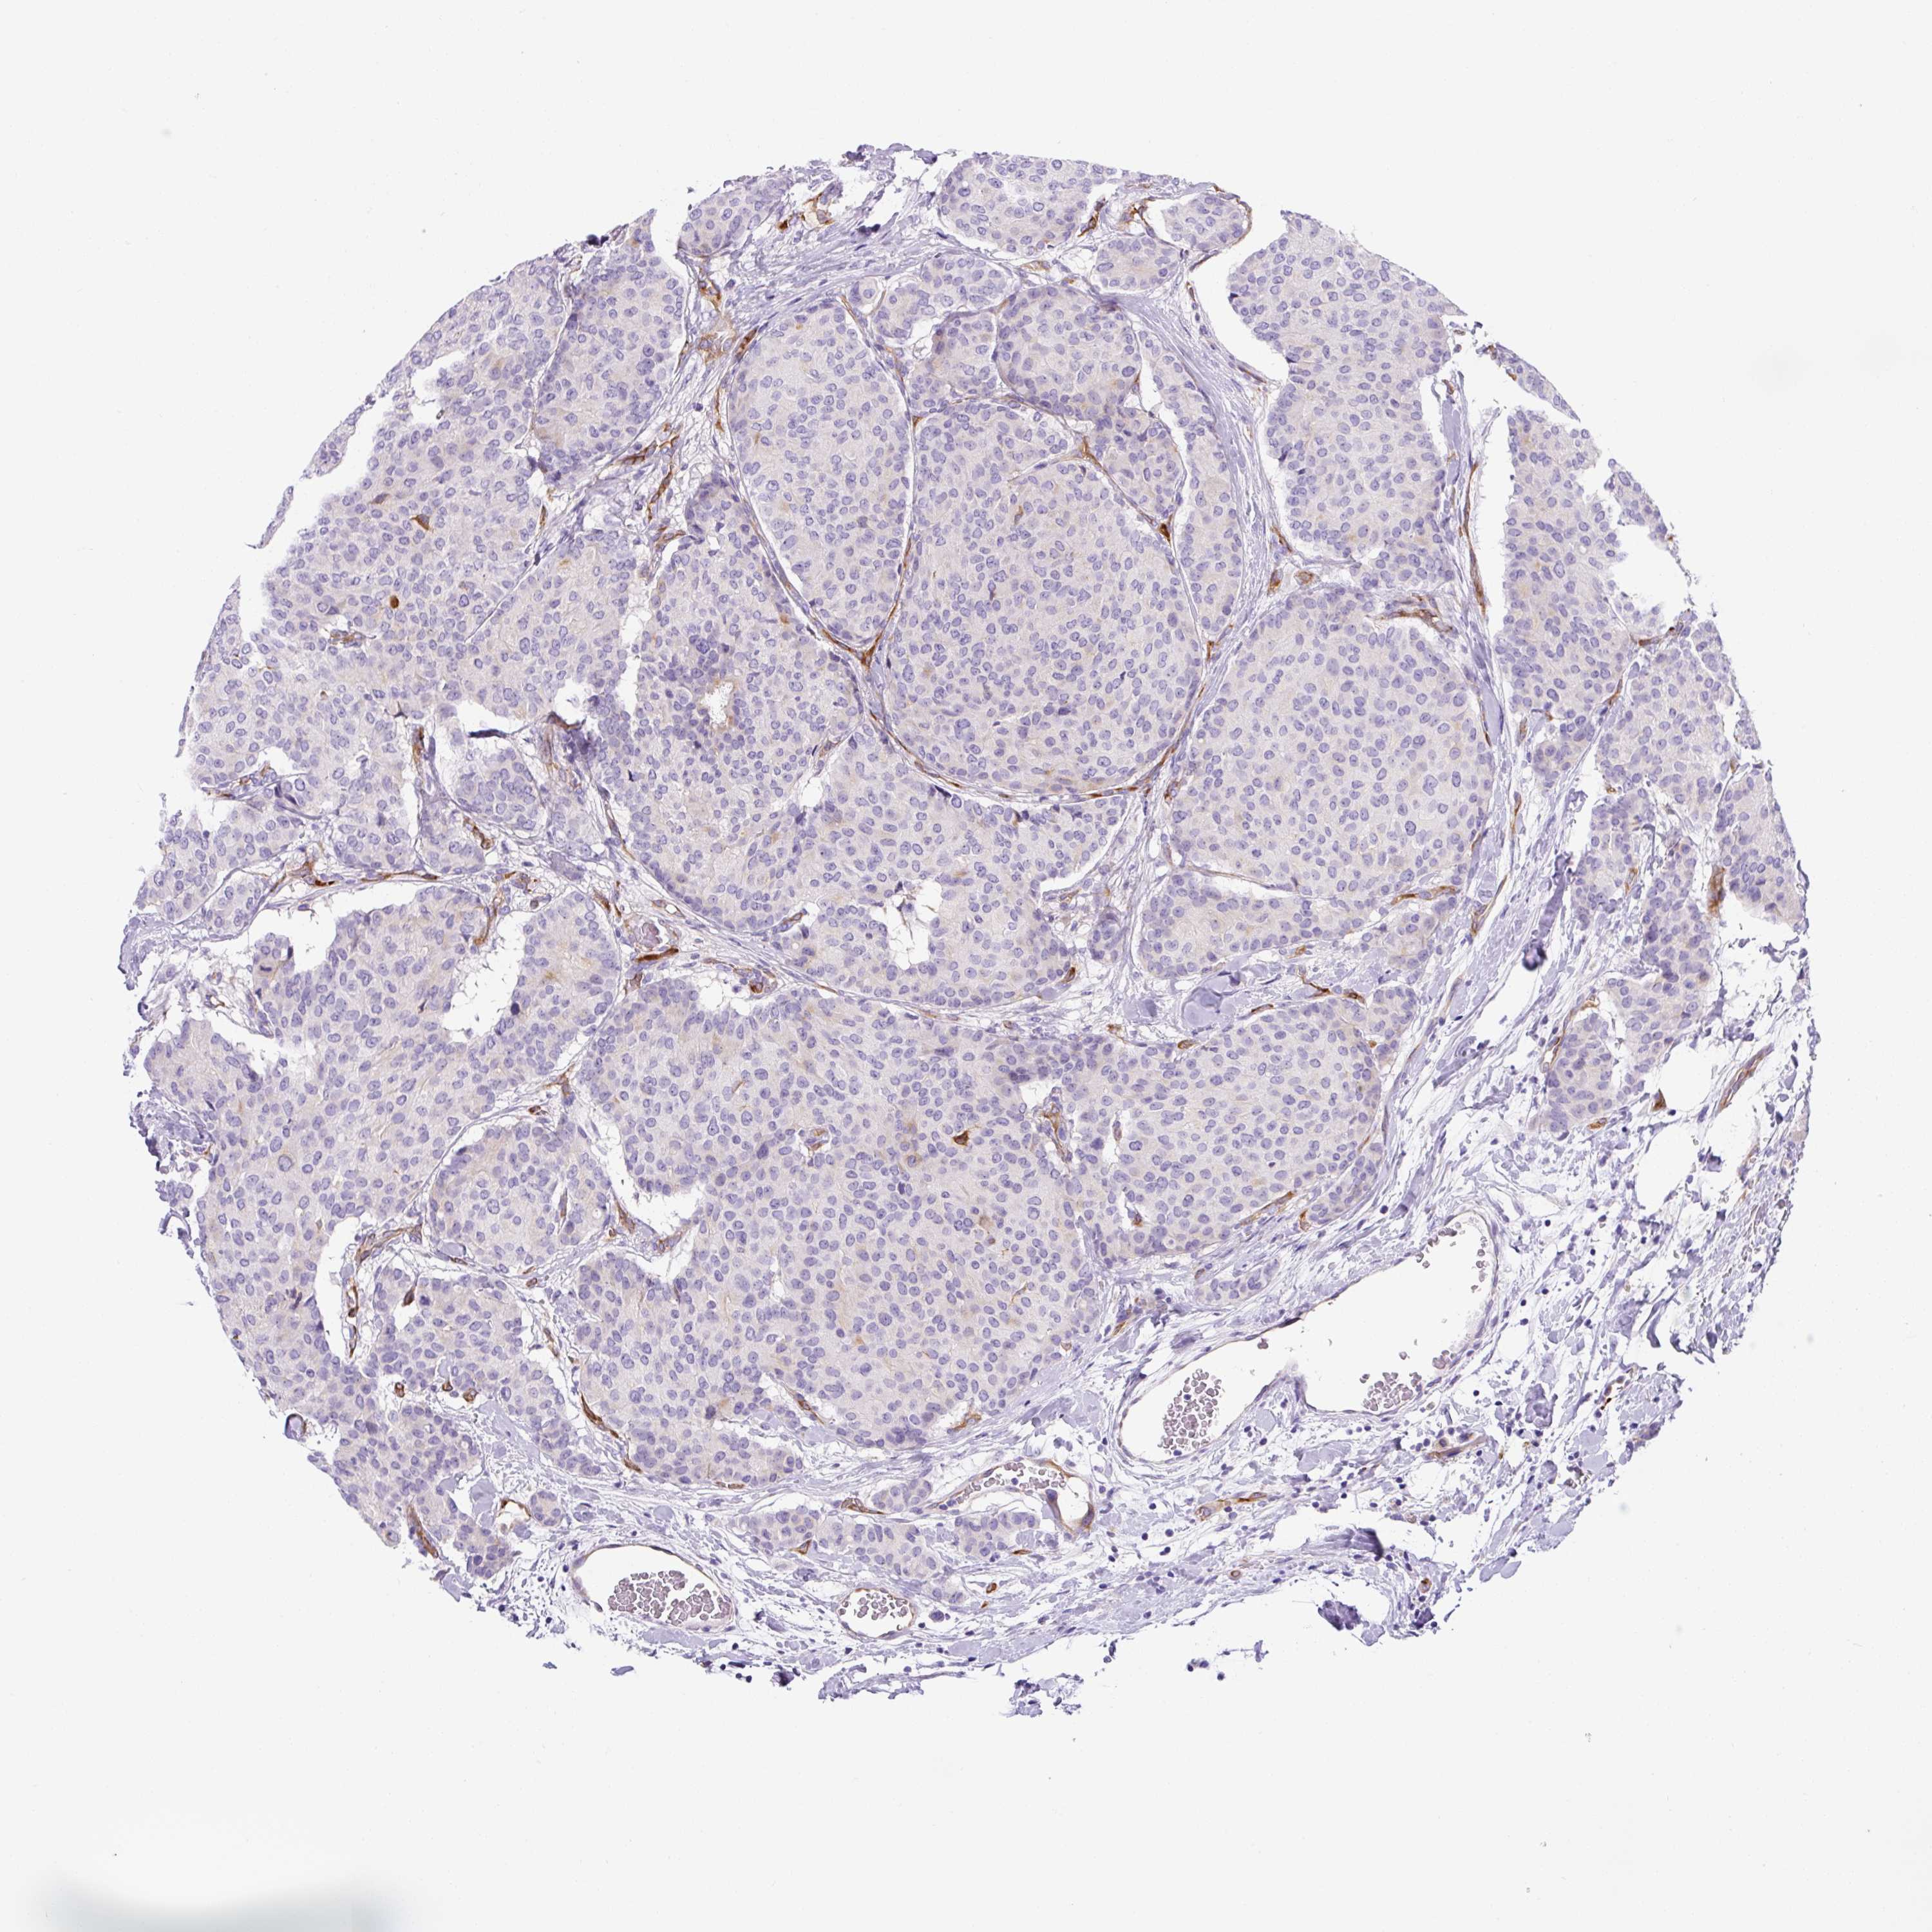

CANCER BREAST CANCER Show tissue menu

BRCA TCGA BRCA VALIDATION PROTEIN EXPRESSION